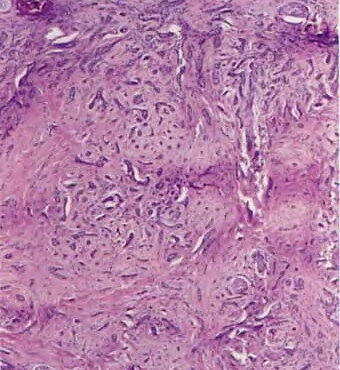

Read Moreminocycline-pigmentation OLYMPUS DIGITAL CAMERA OLYMPUS DIGITAL CAMERA